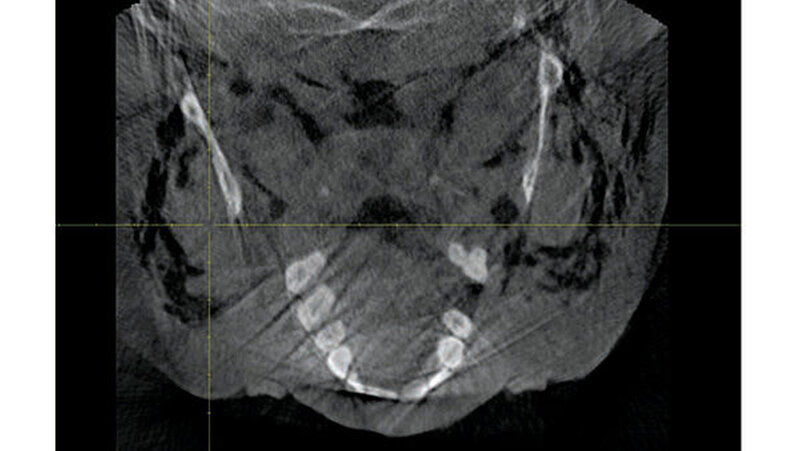

Zum Ausschluss einer Mittelgesichtsfraktur bei palpatorischem Weichteilemphysem erfolgte zur weiteren Diagnostik eine DVT-Aufnahme. Es zeigten sich keine Frakturen im Bereich des Mittelgesichts oder der Kiefer. Jedoch kam in der DVT-Bildgebung sowie der OPT-Optik ein massives Weichgewebeemphysem zur Darstellung (Abbildungen 2 bis 5).